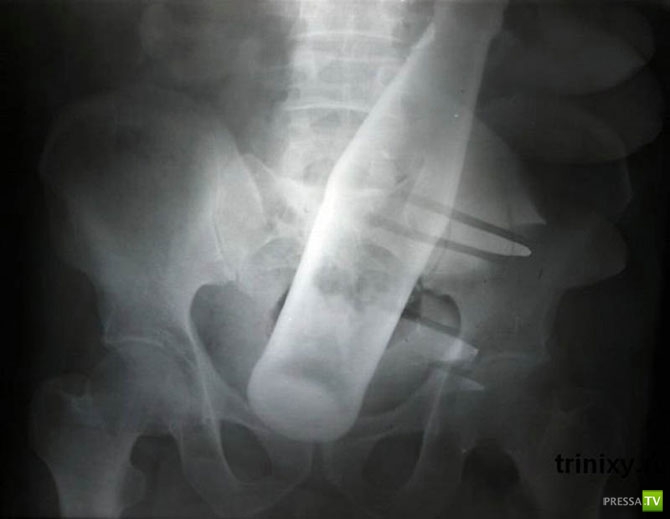

Бутылка из-под «Пепси» в анусе 60-летнего мужчины.